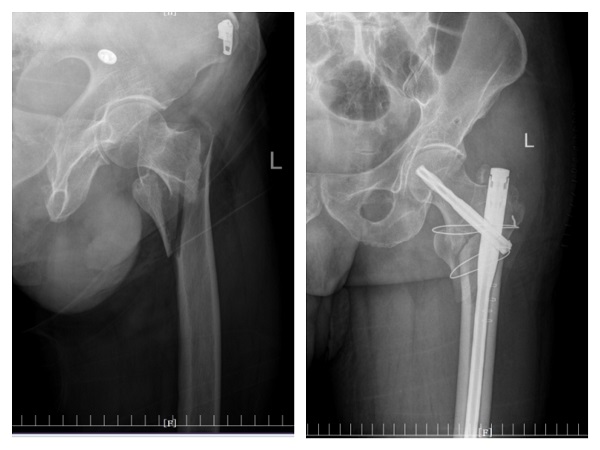

许爷爷今年83岁,不慎摔伤致左髋部疼痛入住陕健医二一五医院骨五科,完善检查发现许爷爷新冠病毒检测为阳性,肺部已有感染。由于年事已高,有基础病且合并新冠病毒感染,病情复杂危重,情况非常棘手。骨五科潘建宏主任团队为许爷爷进行了全面细致的病情评估,并请院内相关专家组会诊,制定了有针对性的治疗方案。

入院一周后,肺部感染逐渐得到控制,氧饱和度正常后,潘主任团队为许爷爷进行左侧人工股骨头置换术,手术十分顺利。术后,科室医护人员密切关注老人的神志、呼吸和各项生命体征变化,及时根据病情变化调整治疗方案,并加强肺功能锻炼。术后三天,许爷爷能够在助行器辅助下下床行走,无明显不适,生命体征平稳。在科室医护团队日夜精心的照料下,许爷爷日见好转,说话声音开始响亮,浑身也有了力气,其家属表示深深地感谢,经过半个多月的精心治疗,许爷爷现已康复出院。